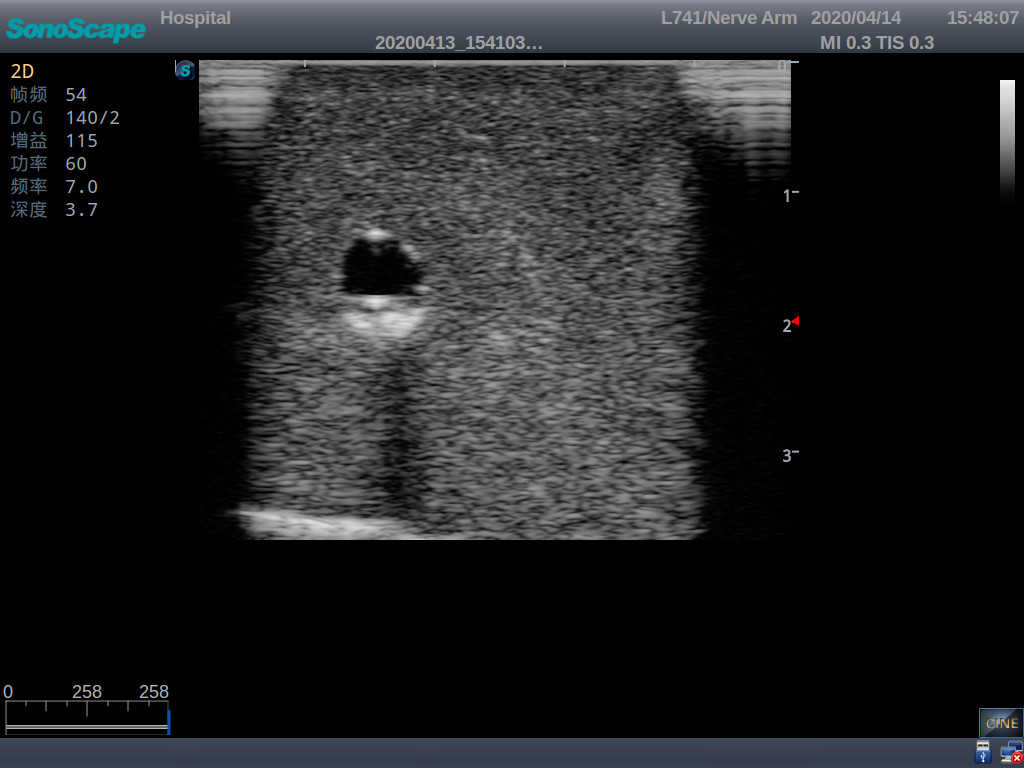

3)   Clear and real images of the tissues and organs (basilic vein and superior vena cava)